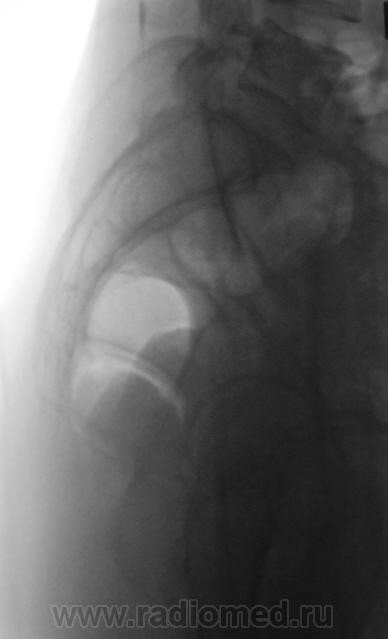

Из анамнеза известно, что примерно 2 месяца тому "летела" со сноутборга около 200 метров. Сейчас беспокоят боли в области спины, крестца и лонного сочленения. УЗИ было сделано всего, что только можно, везде - "норма". Хирурги, вроде-бы тоже ничего не находят. Но боли, видать значительные, походка вынужденная. На рентгенографию была направлена, как жест отчаяния, мол может быть, что-то найдут.

Рентгенограмма в прямой проекции.

1. Не исключаю поперечный перелом S5.

2. Лонное сочленение очевидно,подверглось значительному растяжению (имеется локальный вакуум-феномен слева), умеренно выраженые явления симфизита (опять же - постравматического).

1. По первым снимкам не отпускало впечатление о повреждении левого крестцово-подвздошного сочленения. После подготовки вроде-бы все нормально, но все равно что-то гложет.

2. А на боковой массе крестца справа разве не линия консолидирующегося перелома?